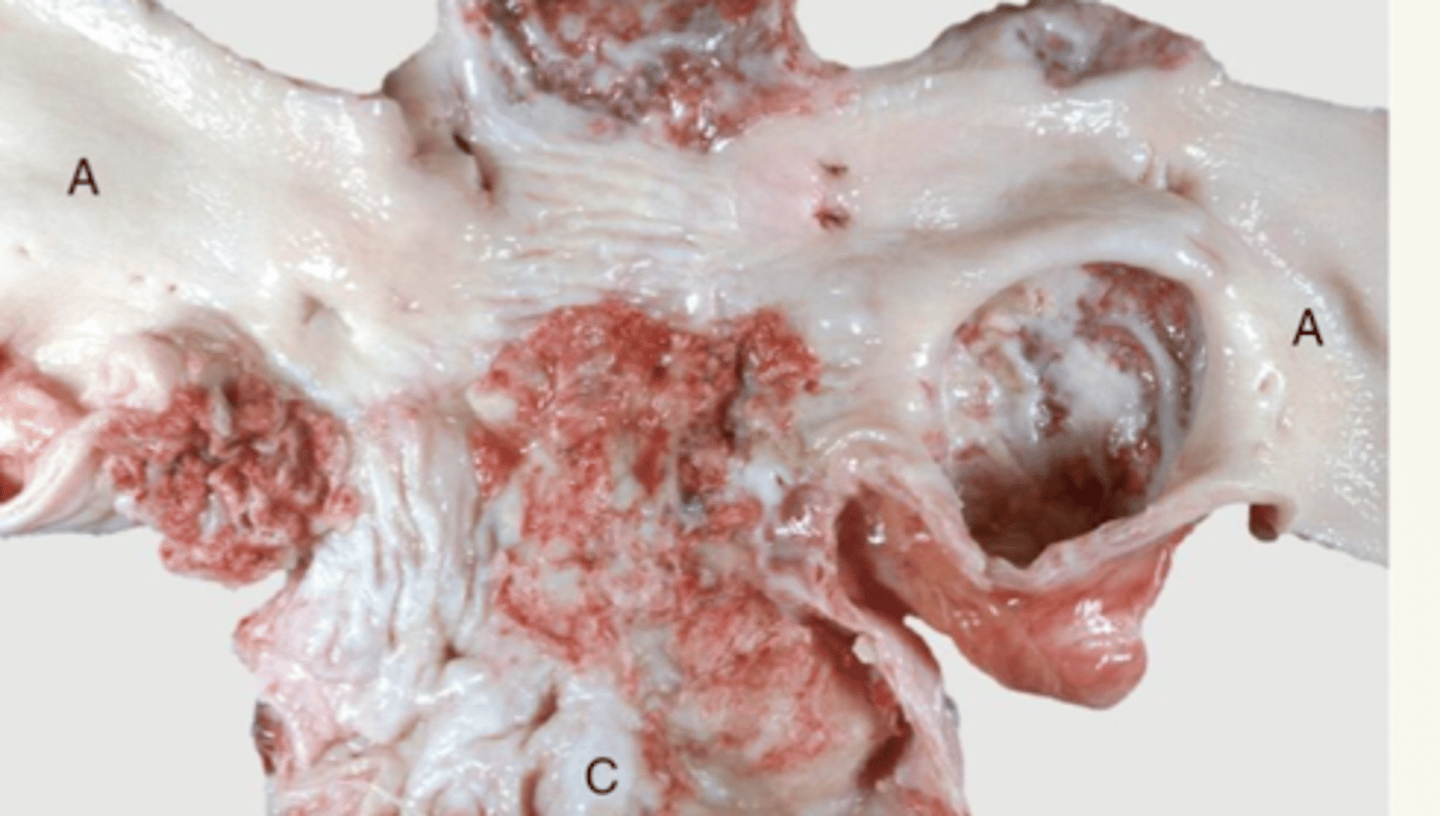

enteritis piogranulomatosa

Rhodococcus equi

(bacteria pulmonar, que puede llegar al intestino y formar lesiones purulentos y granulomatosos))

¿patología morfológica y etiológica?

¿patología morfológica y etológica?